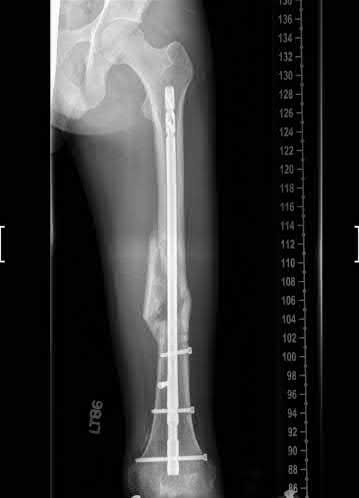

Question 17

A 32-year-old male sustains a closed tibia fracture and develops intense leg pain out of proportion to the injury. You suspect acute compartment syndrome.

Which of the following pressure parameters is considered the most reliable threshold indication for performing a four-compartment fasciotomy?

Explanation